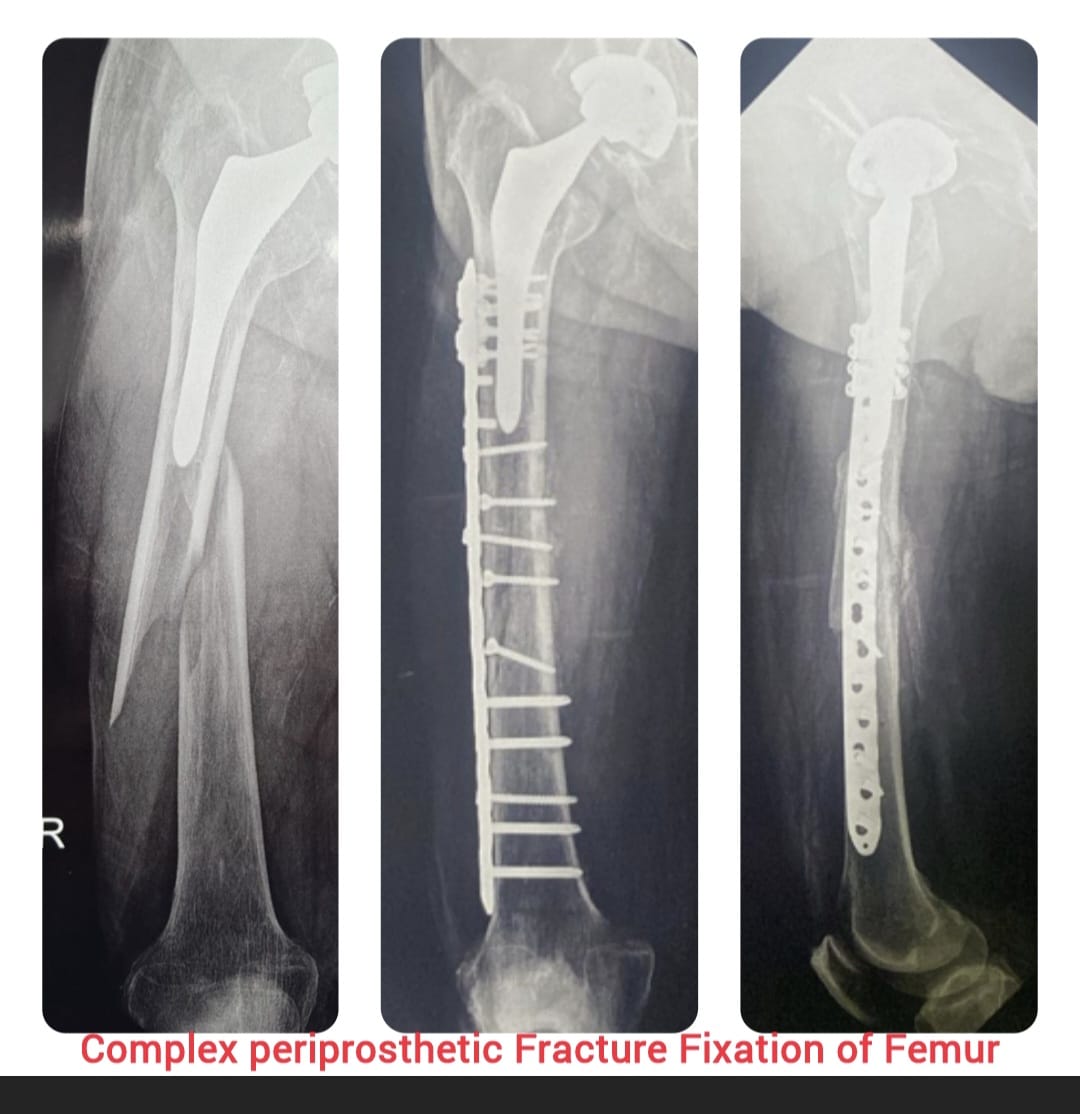

Diagnosis begins with detailed clinical evaluation supported by advanced imaging such as X-rays, CT scans, and MRI. Treatment options are customized based on the type and severity of injury and may include casting, splinting, closed reduction, or surgical intervention to restore proper alignment and stability.